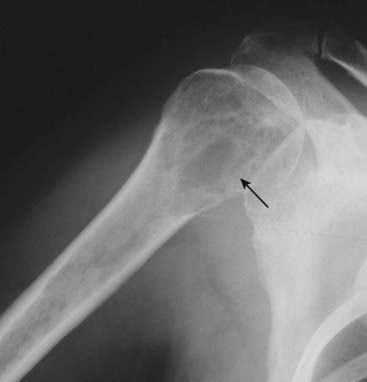

The important exception is multiple myeloma. Bone scans will frequently be negative because of the almost purely lytic nature of multiple myeloma unless there is an associated pathologic fracture. Conventional radiographs of the axial and proximal appendicular skeleton (a bone or metastatic survey) may be more useful in this disease than a bone scan (Fig. 3).

image

Figure 3 Multiple myeloma on conventional radiography.

Bone scans will frequently be negative in multiple myeloma because of the almost purely lytic nature of the lesions (solid black arrow) unless there is an associated pathologic fracture. Conventional radiographs of the axial and proximal appendicular skeleton (most often called a bone or metastatic survey) may be more diagnostic in this disease than a bone scan.